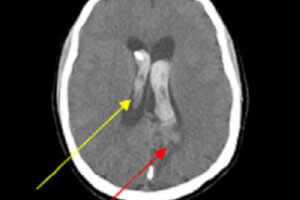

Acute Infarct on CT

The recent use of intravenous tissue plasminogen activator (TPA) to treat acute stoke has resulted in the introduction of “code strokes” in many emergency rooms, which typically require the coordinated efforts of... Read more »